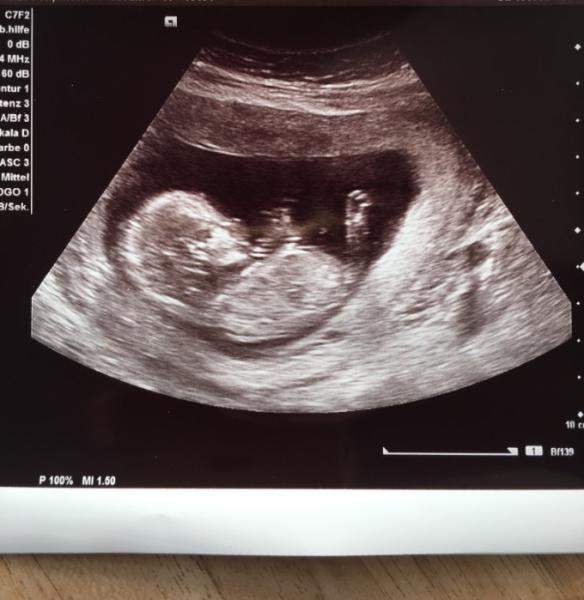

Waren heute morgen zur Vorsorge. Und Baby Boy geht es super. Er hat mächtig gezappelt und alles sieht gut aus. Bin jetzt bei 13+3 aber alles Messungen ergaben 14+5 sie will bis zur 20. Woche warten und den termin dann ggf korrigieren. Das wird wohl kein März Baby sondern Februar.

Bild zu Heute vorsorge - Forum für März - Mamis

Super, dass alles in Ordnung ist und süßes Bild